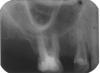

ИринаИ Опубликовано 13 февраля, 2007 Поделиться Опубликовано 13 февраля, 2007 Многоуважаемые профессионалы! Пожалуйста, не откажите посмотреть прилагаемые снимки и помочь с диагнозом. Сейчас я имею их 3 - и проблема в том, что они взаимоисключающие в отношении тактики лечения. Мне 46 лет. Располагаю только 18ю зубами. Каждый уже дорог. Т.к. появились проблемы с ВНЧС, 2 недели назад обратилась к врачу , чтобы санировать зубы перед протезированием, и, как мне свойственно, с ходу вляпалась в проблему.Речь о зубе, с которого мы с врачом начали – 24м. Была старая пломба (снимок 01 – до начала лечения), начали снимать – боль, вскрыта пульпарная камера, пройдены 2 канала, поставлен каласепт. Диагноз врача – периодонтит, хронический, м.б. и травматический ( на зубок шла основная нагрузка , тк у него – редкий случай в моем беззубом рту!-есть антагонист ). В течение недели – боль, почти постоянная, резкая при надавливании и накусывании , особенно со стороны «внутренней» стороны коронки зуба. В этот момент- см. снимки «на каласепте»02 и 03. Открыт зуб, расширены каналы, они «чистые», пройдены до конца. Поставлены турунды(так-?) с рокалем. Ибупрофен 400мг 3 р в день 4 дня. Через 6 дней боль вроде утихла, но в течении недели была небольшая припухлость над зубом на уровне крыла носа. Но – когда я обратилась на всякий случай за консультацию к парадонтологу, -та задумалась над снимками, позвала хирурга- имплантолога и они вместе констатировали: «24 зуб под временной пломбой. Перкуссия безболезненна. При пальпации подвижность дистальной стенки.»поставили диагноз: «24 зуб- …в нижней трети корня неравномерный перелом( горизонтально).Рекомендовано удаление 24 зуба . С пародонтитом изменения в костной ткани не связаны». Мой врач-терапевт не видит перелома. (Увы, она работает в частном кабинете без рентгена и я ношу ей снимки из клиники, в к-рой увидели перелом). Сегодня сделала еще 2 снимка «на рокале» 04,05.Не хочу остаться беззубой старушонкой!!!!!-тк ещё и 26й, плохо, как оказалось, запломбированный 10 лет назад уже со свищом – на удаление, так? Обратилась сегодня ещё к 3м хирургам, предъявила зуб и снимки – один говорит –не вижу перелома, но есть большая гранулема(!), не вылечить. Два других не видят перелома, предлагают пробовать лечить, но сомневаются в успехе из-за «большой резорбции костной ткани—так?- могу переврать). Все доктора, кроме «гранулёмщика» производят впечатление профессионалов, и я в смятении.Так есть перелом или нет???То есть- Лечить или не лечить, а удалять??? И если удалять, то какой в первую очередь – 24 или 26? Пожалуйста, откликнитесь. Старалась писать сухо и по делу, но очень переживаю, т.к. 10 лет назад на этой стороне лица после стоматологического лечения у меня в течение 1,5 лет были зубные боли, причину которых не смогли уверенно определить, и, ясно дело, постфактум лечили уже соматизированную депрессию. Это был трудный опыт выживания, и зря травмировать эту часть лица я очень, очень боюсь. Спасибо.Ирина. Ссылка на комментарий

Skip Опубликовано 13 февраля, 2007 Поделиться Опубликовано 13 февраля, 2007 Многоуважаемые профессионалы! Пожалуйста, не откажите посмотреть прилагаемые снимки и помочь с диагнозом. Сейчас я имею их 3 - и проблема в том, что они взаимоисключающие в отношении тактики лечения. Мне 46 лет. Располагаю только 18ю зубами. Каждый уже дорог. Т.к. появились проблемы с ВНЧС, 2 недели назад обратилась к врачу , чтобы санировать зубы перед протезированием, и, как мне свойственно, с ходу вляпалась в проблему. Речь о зубе, с которого мы с врачом начали – 24м. Была старая пломба (снимок 01 – до начала лечения), начали снимать – боль, вскрыта пульпарная камера, пройдены 2 канала, поставлен каласепт. Диагноз врача – периодонтит, хронический, м.б. и травматический ( на зубок шла основная нагрузка , тк у него – редкий случай в моем беззубом рту!-есть антагонист ). В течение недели – боль, почти постоянная, резкая при надавливании и накусывании , особенно со стороны «внутренней» стороны коронки зуба. В этот момент- см. снимки «на каласепте»02 и 03. Открыт зуб, расширены каналы, они «чистые», пройдены до конца. Поставлены турунды(так-?) с рокалем. Ибупрофен 400мг 3 р в день 4 дня. Через 6 дней боль вроде утихла, но в течении недели была небольшая припухлость над зубом на уровне крыла носа. Но – когда я обратилась на всякий случай за консультацию к парадонтологу, -та задумалась над снимками, позвала хирурга- имплантолога и они вместе констатировали: «24 зуб под временной пломбой. Перкуссия безболезненна. При пальпации подвижность дистальной стенки.»поставили диагноз: «24 зуб- …в нижней трети корня неравномерный перелом( горизонтально).Рекомендовано удаление 24 зуба . С пародонтитом изменения в костной ткани не связаны». Мой врач-терапевт не видит перелома. (Увы, она работает в частном кабинете без рентгена и я ношу ей снимки из клиники, в к-рой увидели перелом). Сегодня сделала еще 2 снимка «на рокале» 04,05.Не хочу остаться беззубой старушонкой!!!!!-тк ещё и 26й, плохо, как оказалось, запломбированный 10 лет назад уже со свищом – на удаление, так? Обратилась сегодня ещё к 3м хирургам, предъявила зуб и снимки – один говорит –не вижу перелома, но есть большая гранулема(!), не вылечить. Два других не видят перелома, предлагают пробовать лечить, но сомневаются в успехе из-за «большой резорбции костной ткани—так?- могу переврать). Все доктора, кроме «гранулёмщика» производят впечатление профессионалов, и я в смятении. Так есть перелом или нет??? То есть- Лечить или не лечить, а удалять??? И если удалять, то какой в первую очередь – 24 или 26? Пожалуйста, откликнитесь. Старалась писать сухо и по делу, но очень переживаю, т.к. 10 лет назад на этой стороне лица после стоматологического лечения у меня в течение 1,5 лет были зубные боли, причину которых не смогли уверенно определить, и, ясно дело, постфактум лечили уже соматизированную депрессию. Это был трудный опыт выживания, и зря травмировать эту часть лица я очень, очень боюсь. Спасибо.Ирина. Здравствуйте, Ирина. Ситуация достаточно сложная и для того, чтобы дать объективную оценку Вашего случая, необходима конечно же очная встреча... Но, попытка не пытка, может быть мы здесь сообща и попытаемся хоть что-нибуть прояснить. Сначала несколько вопросов: 1. На момент обращения к врачу зуб 24 уже болел? Если да, то опишите характер болей(от температуры, при надавливании, самопроизвольно...) 2. Во время лечения, Ваш врач использовал какой-нибудь электронный прибор для определения длинны канала (т.н. апекслокатор) или ограничивался только тактильным чувством? На снимках сложно что-либо разобрать, но настораживает подвижность части зуба, которую определил хирург. Может быть это и перелом, т.к. в устьевой части и верхней трети каналов, как мне кажется по снимкам, изрядно поработали бором, что могло привести и к перфорации стенки канала. Кистогранулёмы я не нашёл, но вот на одном участке поверхности корня, ближе к коронке зуба и обрщённого к клыку, предположительно имеет место ограниченная резорбция корня (рассасывание). Совет на будущее. Зубы старайтесь лечить там, где есть возможность сделать рентген, т.к. делать это приходиться непосредственно во время лечения... Ссылка на комментарий